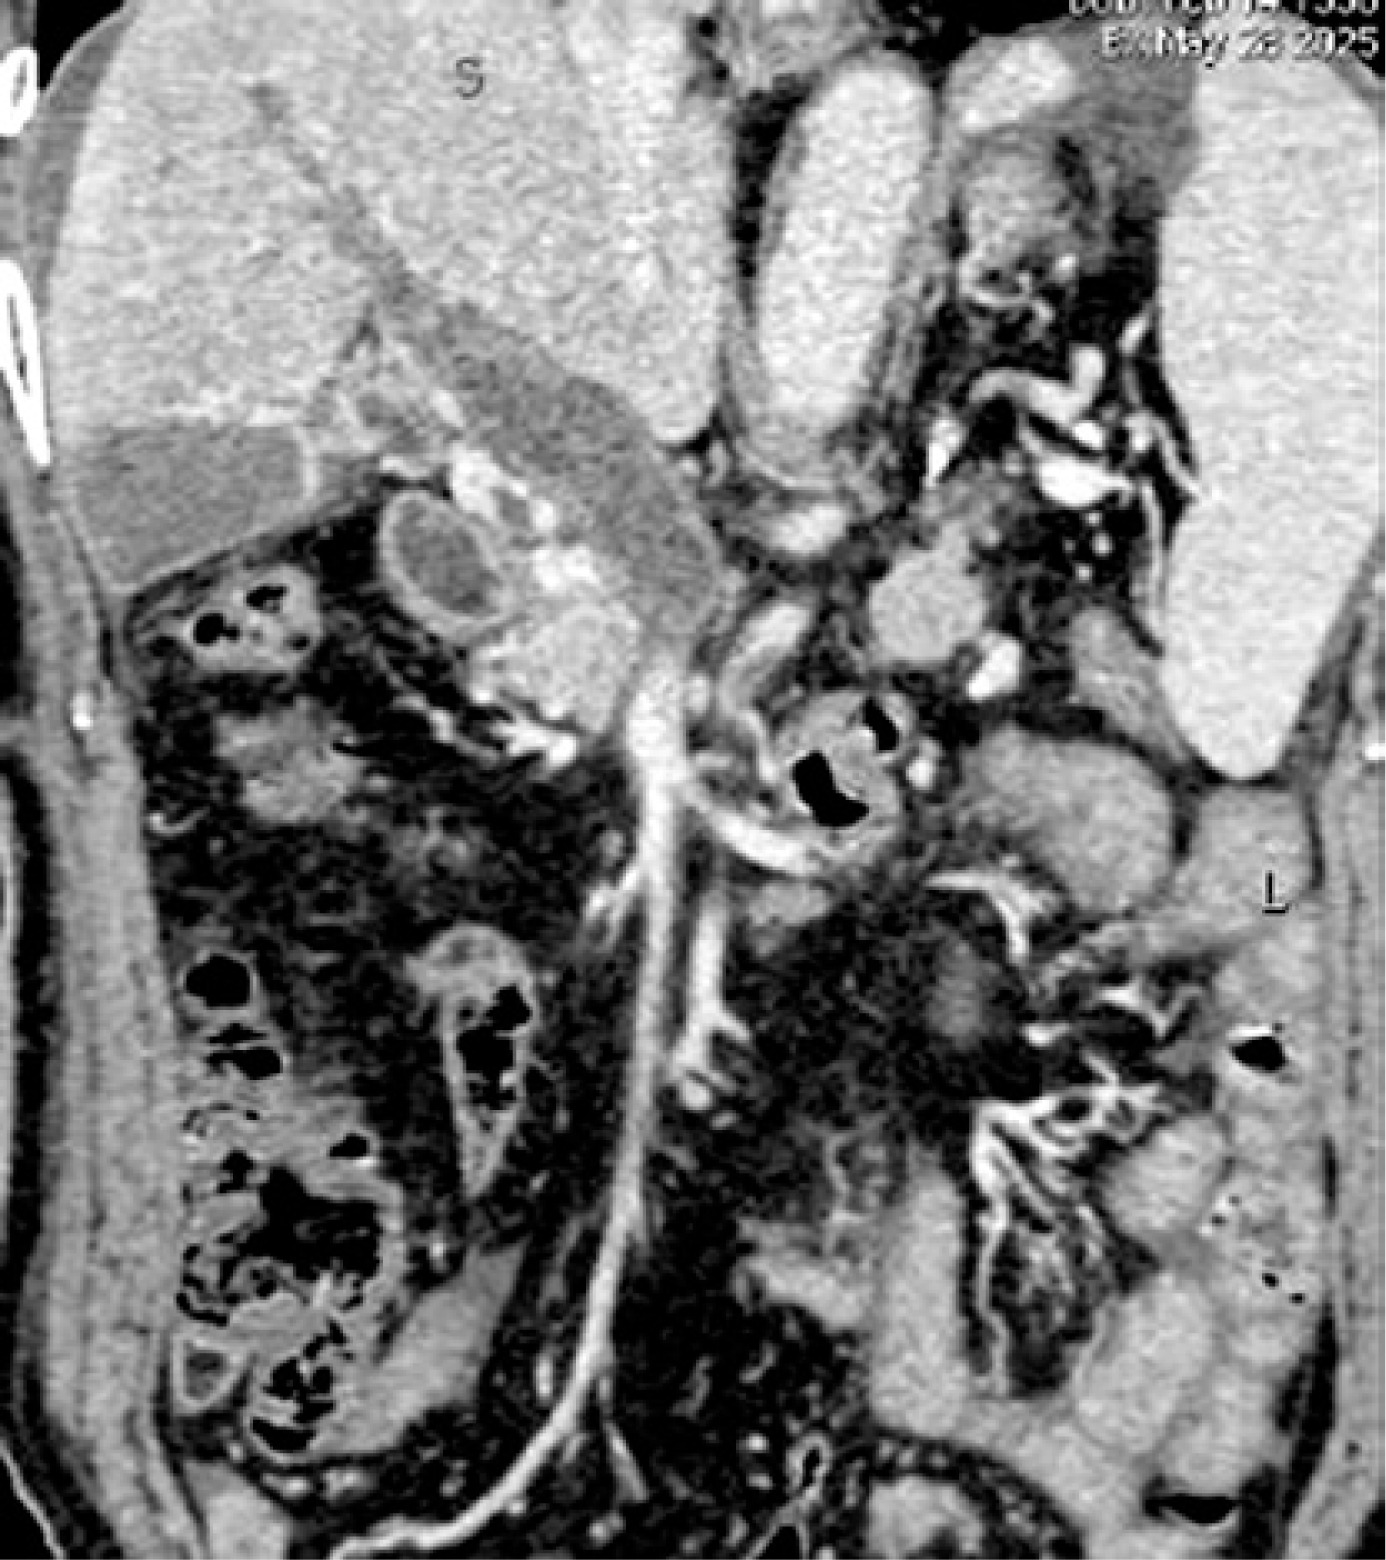

On May 28, laboratory tests showed that D-dimer was 19.58 mg/l (reference range: 0.00–0.55 mg/l), fibrinogen degradation products (FDP) was 60.92 µg/ml (reference range: 0.0–5.0 µg/ml), white blood cell count was 6.2 × 109/l, red blood cell count was 4.47 × 1012/l, hemoglobin level was 134 g/l, percentage of basophilic granulocytes was 0.5%, platelet count was 87 × 109/l (reference range: 125–350 × 109/l), haematocrit was 0.402 l/l, lactate dehydrogenase level was 222 u/l, serum direct bilirubin was 6.9 µmol/l, and indirect bilirubin was 8.7 µmol/l. Abdominal contrast-enhanced CT scans indicated portal hypertension, esophagogastric varices, and occlusive thrombosis in the portal vein (Figure 1). Subsequently, low-molecular-weight heparin sodium (LMWH) was administered subcutaneously at a dose of 5000 IU every 12 h.